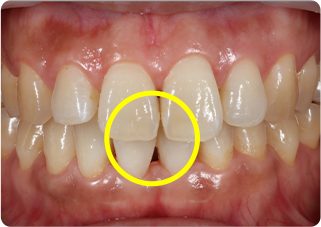

上唇小帯切除症例

術前

術後

| 主訴 | 上の前歯のすきっ歯が気になる |

|---|---|

| 治療期間/回数 | 1ヵ月、3回 |

| 価格(税込) | 保険適応 |

| リスク・副作用 | 出血、術後疼痛の可能性 |

| ポイント | 上唇小帯の付着異常により、正中離開が起きていた。上唇小帯を電気メスで切除した結果、歯を正中に寄せることが出来た。 |